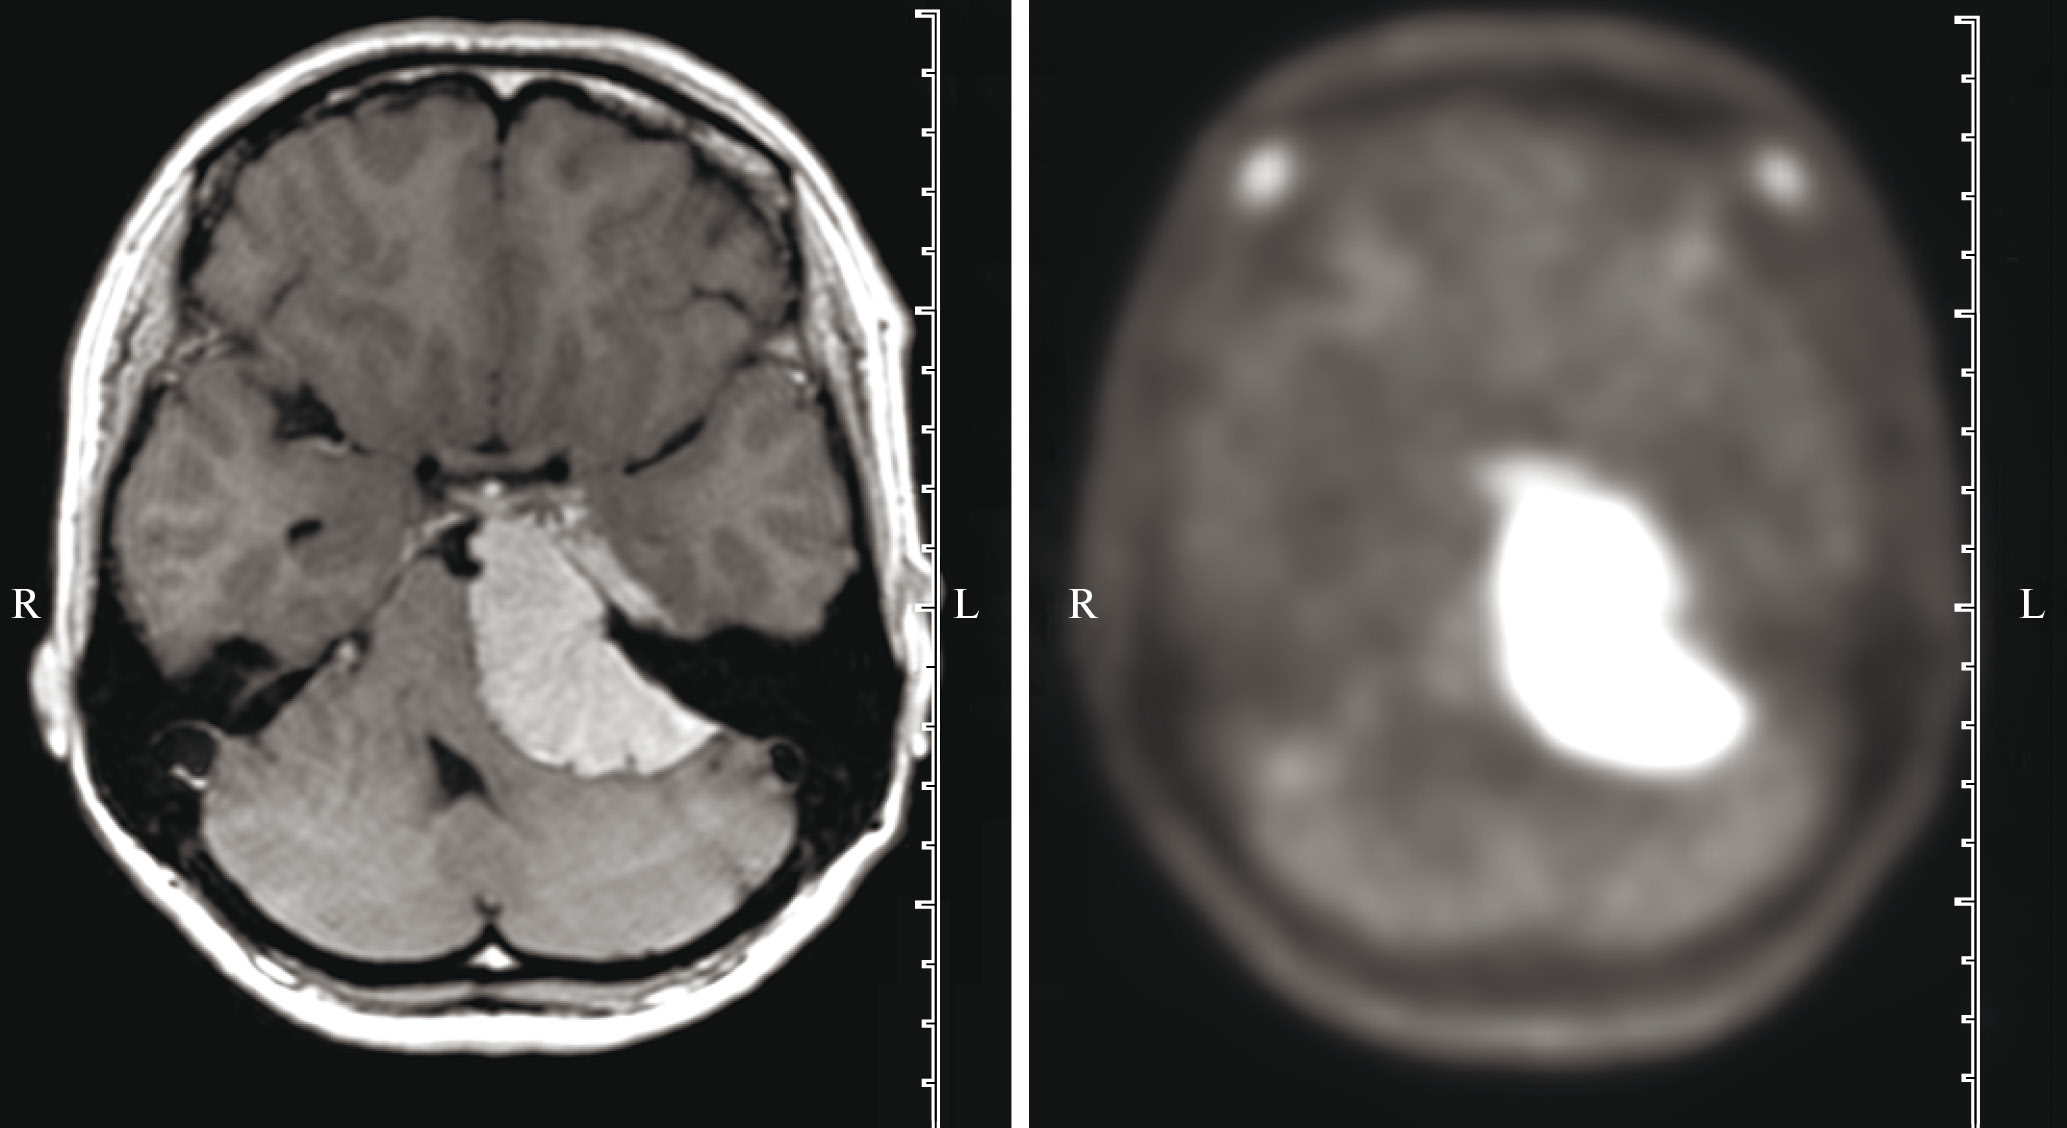

Медиана индекса накопления11С–МЕТ в менингиомах степеней 0, 1, 2 и 3 составила 2.24 [1.68; 2.99], 4.06 [3.04; 4.57], 2.32 [2.12; 3.69] и 4.29 [2.60; 5.10] соответственно. Отметим, что даже гистологически верифицированные доброкачественные менингиомы 1-й степени по классификации ВОЗ часто демонстрировали высокий ИН РФП (рис. 1). При попарном сравнении было выявлено, что ИН РФП в менингиомах степени 0 достоверно меньше, чем в менингиомах 1-й степени (p < 0.001) и в менингиомах 3-й степени (p = 0.032). ИН в гистологически верифицированных менингиомах 1, 2 и 3-й степеней злокачественности по шкале ВОЗ достоверно не отличался. Сопоставление ИН 11С–МЕТ в менингиомах 1-й степени (4.06 [3.04; 4.57]) и менингиомах 0 и 1-й степеней (2.63 [1.81; 3.82]) с менингиомами 2 и 3-й степеней (3.11 [2.28; 4.49]) не выявило статистически значимого отличия. Результаты сопоставления не изменились после исключения из групп сопоставления опухолей, которые ранее подверглись лучевому лечению.

Рис. 1. Петрокливальная менингиома степени 1 по классификации ВОЗ на МРТ (слева) и ПЭТ/КТ с 11С-метионином (справа). При ПЭТ/КТ определяется высокий уровень накопления РФП – 5.5.

Fig. 1. WHO grade 1 petroclival meningioma on MRI (left) and PET/CT with 11C-methionine (right). PET/CT shows a high tumor-to-brain ratio of 5.5.